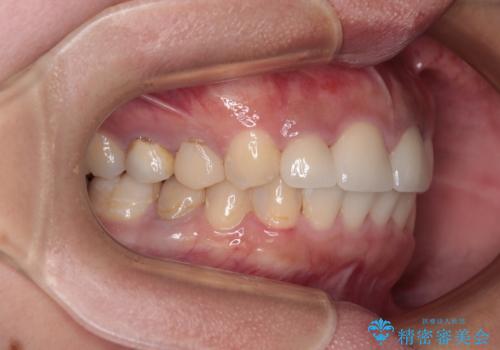

歯列から飛び出た歯 ワイヤー矯正で整った歯列に

- 下顎の歯列から飛び出した小臼歯を気にして来院された患者様です。

歯列以外に、上顎左右側切歯が矮小歯であり、上顎4前歯は失活していたため、矯正治療で歯列を整えるとともに上顎前歯の幅を調整し、矯正治療後にオールセラミッククラウンにて審美歯科治療を行うこととしました。

下顎の小臼歯を移動しきるのに2年弱の期間を要することとなり、補綴治療も合わせて2年半ほどの治療期間となりました。

口元の印象が大きく改善し、患者様には大変満足していただけました。